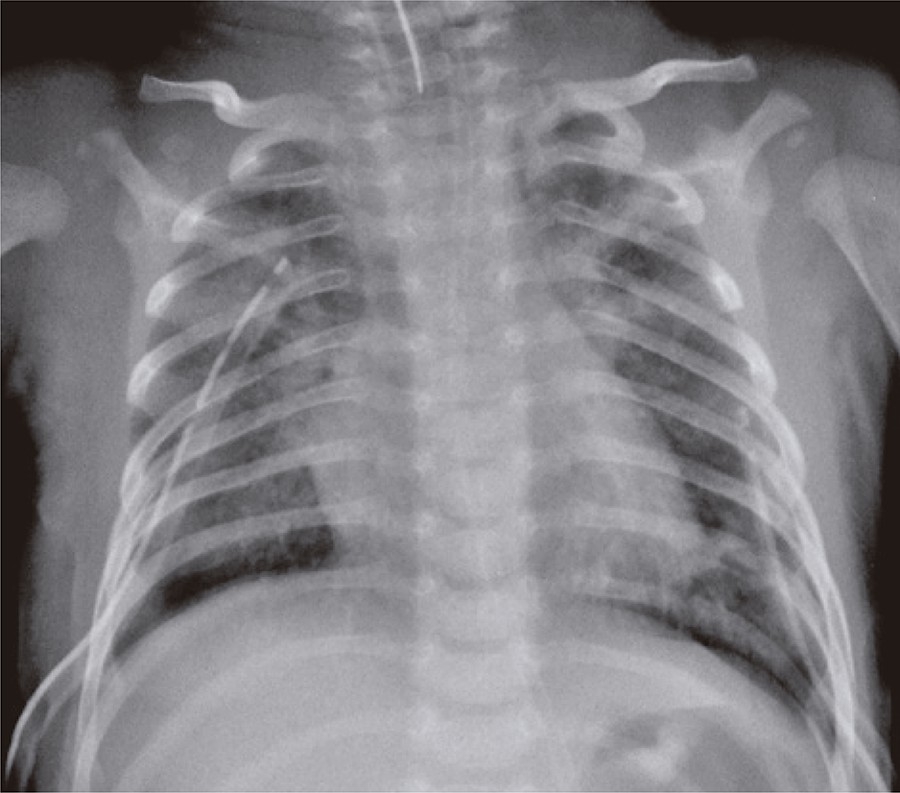

A 37-days-old baby boy, previously healthy and without intercurrences during perinatal period, who was admitted in pediatric intensive care unit with acute ventilator insufficiency because of viral bronchiolitis due to respiratory syncytial virus. The patient underwent a tracheal intubation by clinical deterioration, a rapid sequence intubation using fentanyl, ketamine and succinylcholine. During the procedure, he had cough, chest rigidity, reduction of respiratory sounds and poor tissue perfusion. His clinical picture worsened and resulted in cardiorespiratory arrest in asystole that was reverted with chest compressions and two doses of intravenous epinephrine. Subsequently, the patient showed a new cardiorespiratory arrest, and he was under risk for hypertensive pneumothorax. A relief thoracentesis was carried out and significant improvement was observed in respiratory sound and signs of poor peripheral perfusion. After bilateral thoracic drainage the patient had ventilator parameters reduced, however, this reduction remained with impaired tissue perfusion, mottled skin, fine pulses, hypotension, and cardiac auscultation with hypophonesis sound. The chest radiology exam confirmed hypertensive pneumopericardium () that resolved with pericardiocenthesis and drainage of 40mL of pericardium air space (). The patient had good clinical progress after underwent the procedure, remained in mechanical ventilation for 6 days, and he was discharged 13 days after the procedure without apparent sequelae.